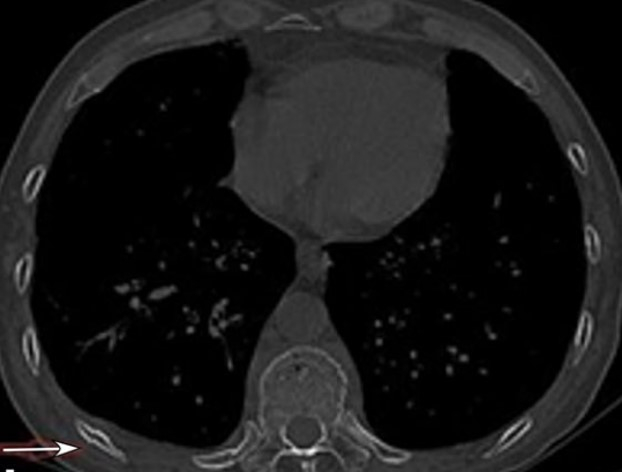

小知识2:CT可以更好地发现肋骨骨折,但是每个人双侧的肋骨有22-26根,单侧11-13根不等。而且肋骨的形态个体差异大,即使有经验的医生在诊断骨折时也需要非常地仔细。打个比方:诊断肋骨骨折就像翻阅一本500页的书,骨折的信息会隐藏在这500页中的任意一页,必须每一页都不漏。对于图4中的骨折,经验不足的医生很容易漏诊,往往这种漏诊就是王阿姨找不到痛的原因。

图4白色箭头所指处的弯曲骨折